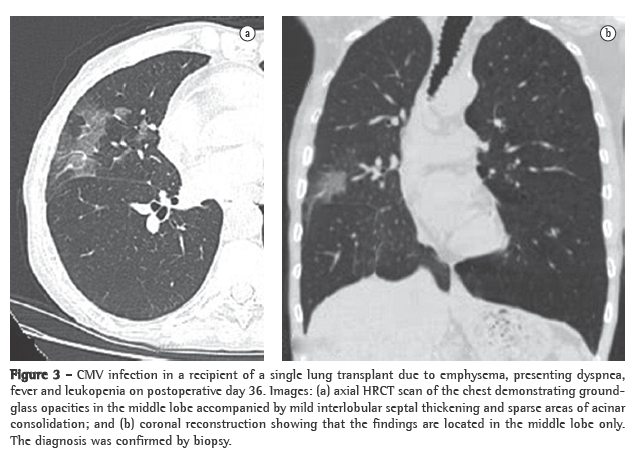

Opportunistic infection occurs in 34-59% of lung transplant recipients.(13) Unfortunately, in patients with new opportunistic pneumonia, chest X-ray findings can be normal, and abnormal findings, when present, are often nonspecific.(11) Cytomegalovirus (CMV) is the most common opportunistic infection among such patients.(14) The incidence of CMV infection peaks between 1 and 2 months after transplantation, most cases occurring between postoperative months 1 and 12.(11,14) Infection with CMV can be primary and secondary. Primary infection occurs in over 90% of CMV seronegative patients receiving a CMV seropositive donor lung and becomes severe in 50-60% of such cases.(11) Secondary infection results from exposure to a different CMV strain or from reactivation of a latent infection in the recipient and is usually less severe than is primary infection.(11) Clinical manifestations of CMV infection include dyspnea, fever, malaise and leukopenia, although many patients with histologically proven CMV pneumonia are asymptomatic.(15) A diagnosis of CMV pneumonia is typically confirmed only after bronchoalveolar lavage and transbronchial biopsy. The radiologic ­manifestations of CMV pneumonia include, as shown in Figure 3, ground-glass opacities, interlobular septal thickening and consolidation, as well as diffuse reticular or reticulonodular opacities, nodules and small areas of effusion.(14) In lung transplant recipients with active CMV infection, chest X-ray findings can be normal,(11) CT scans better depicting the radiological manifestations of the infection, which almost exclusively affects the allograft. The most common CT manifestations are ground-glass opacities, tree-in-bud opacities, airspace consolidation, nodules, interlobular septal thickening, pleural effusions, thickened/enlarged pleura and bronchiectasis.(11-15) Other common viral pulmonary pathogens affecting this population include herpes simplex virus, adenovirus and respiratory syncytial virus.(11)